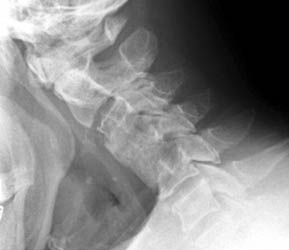

| Lateral flexion and extension views obtained five months after

surgery obtained for surveillance. Note postsurgical changes of anterior fusion

of C3 - C5, however the fusion is not solid at C4 - 5. Movement is detected on

the flexion and extension views at the level of the graft itself. |